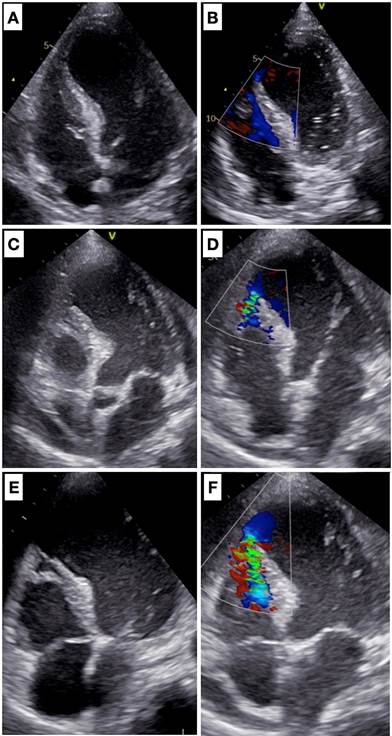

El ETT inicial (Figura 2 A y B) evidenció un ventrículo izquierdo dilatado, con disfunción sistólica severa y adelgazamiento del septum interventricular en el sector anterior apical, sin evidencia del pasaje de flujo. A las 24 horas se evidenció una pequeña CIV anfractuosa a nivel anterior apical, con pasaje de flujo de izquierda a derecha (Figura 2 C y D). Valorado por equipo de cirugía cardíaca, y dada la estabilidad hemodinámica bajo drogas inotrópicas y vasopresoras, se decidió conducta expectante. Los ETT subsiguientes (Figura 2 E y F) evidenciaron progresión del defecto y aumento del tamaño de la CIV. Clínicamente, el paciente se mantuvo estable bajo tratamiento médico.

Figura 2. Evolución ecocardiográfica de la CIV, ventana apical cuatro cámaras en la izquierda y con Doppler color en la derecha. A y B. Imágenes obtenidas al ingreso del paciente. C y D. Imágenes obtenidas a las 24 horas desde el ingreso. E y F. Imágenes obtenidas a las 72 horas desde el ingreso.